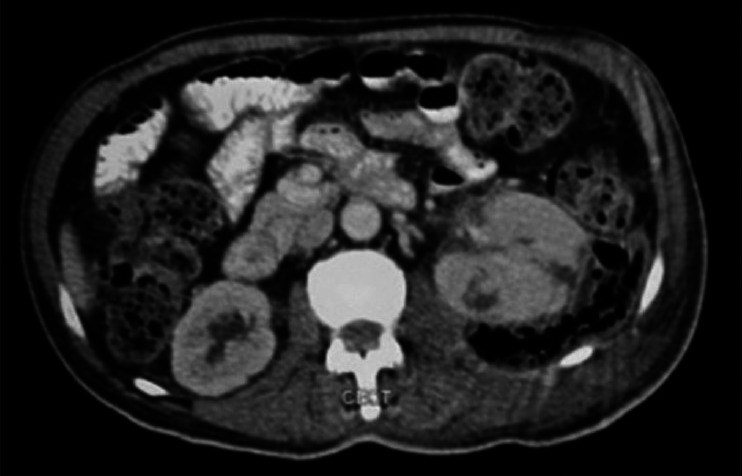

Emphysematous Pyelonephritis (EPN) is a severe, necrotizing, life threatening infection of the renal parenchyma and management is not standardised due to scarcity of literature. We present 3 patients with this rare entity. All 3 patients were of class III on CECT findings based on Huang's classification and had more than two risk factors. Our first patient underwent percutaneous drainage of his condition upon which he recovered. The second and third patients underwent a laparotomy and nephrectomy. The second patient recovered after a stormy post operative period and the third patient died. Management of the first patient was contrary to that recommended in literature, for the other two it was as per recommendations. On successful management of our first patient without surgery and seeing no discernable benefits of surgery for our other two patients, it is possible that percutaneous drainage alone, coupled with antibiotics may be a viable strategy for managing this condition with nephrectomy being considered as a second tier option.

肺气肿性肾盂肾炎(EPN)是一种严重的、坏死性的、危及生命的肾实质感染,由于缺乏文献,其治疗方法尚不规范。我们报告了3例患有这种罕见疾病的患者。根据Huang的分类,所有3例患者的CECT结果均为III级,并且有两个以上的危险因素。我们的第一个病人接受了经皮引流术,他痊愈了。第二名和第三名患者分别进行了剖腹手术和肾切除术。第二例患者术后经历了一段暴风雨期后恢复,第三例患者死亡。第一个病人的治疗方法与文献中推荐的方法相反,另外两个病人的治疗方法与文献中推荐的方法相反。我们的第一个患者成功地进行了手术治疗,而其他两名患者没有明显的手术益处,因此,单独经皮引流联合抗生素可能是治疗这种疾病的可行策略,而肾切除术被认为是第二级选择。